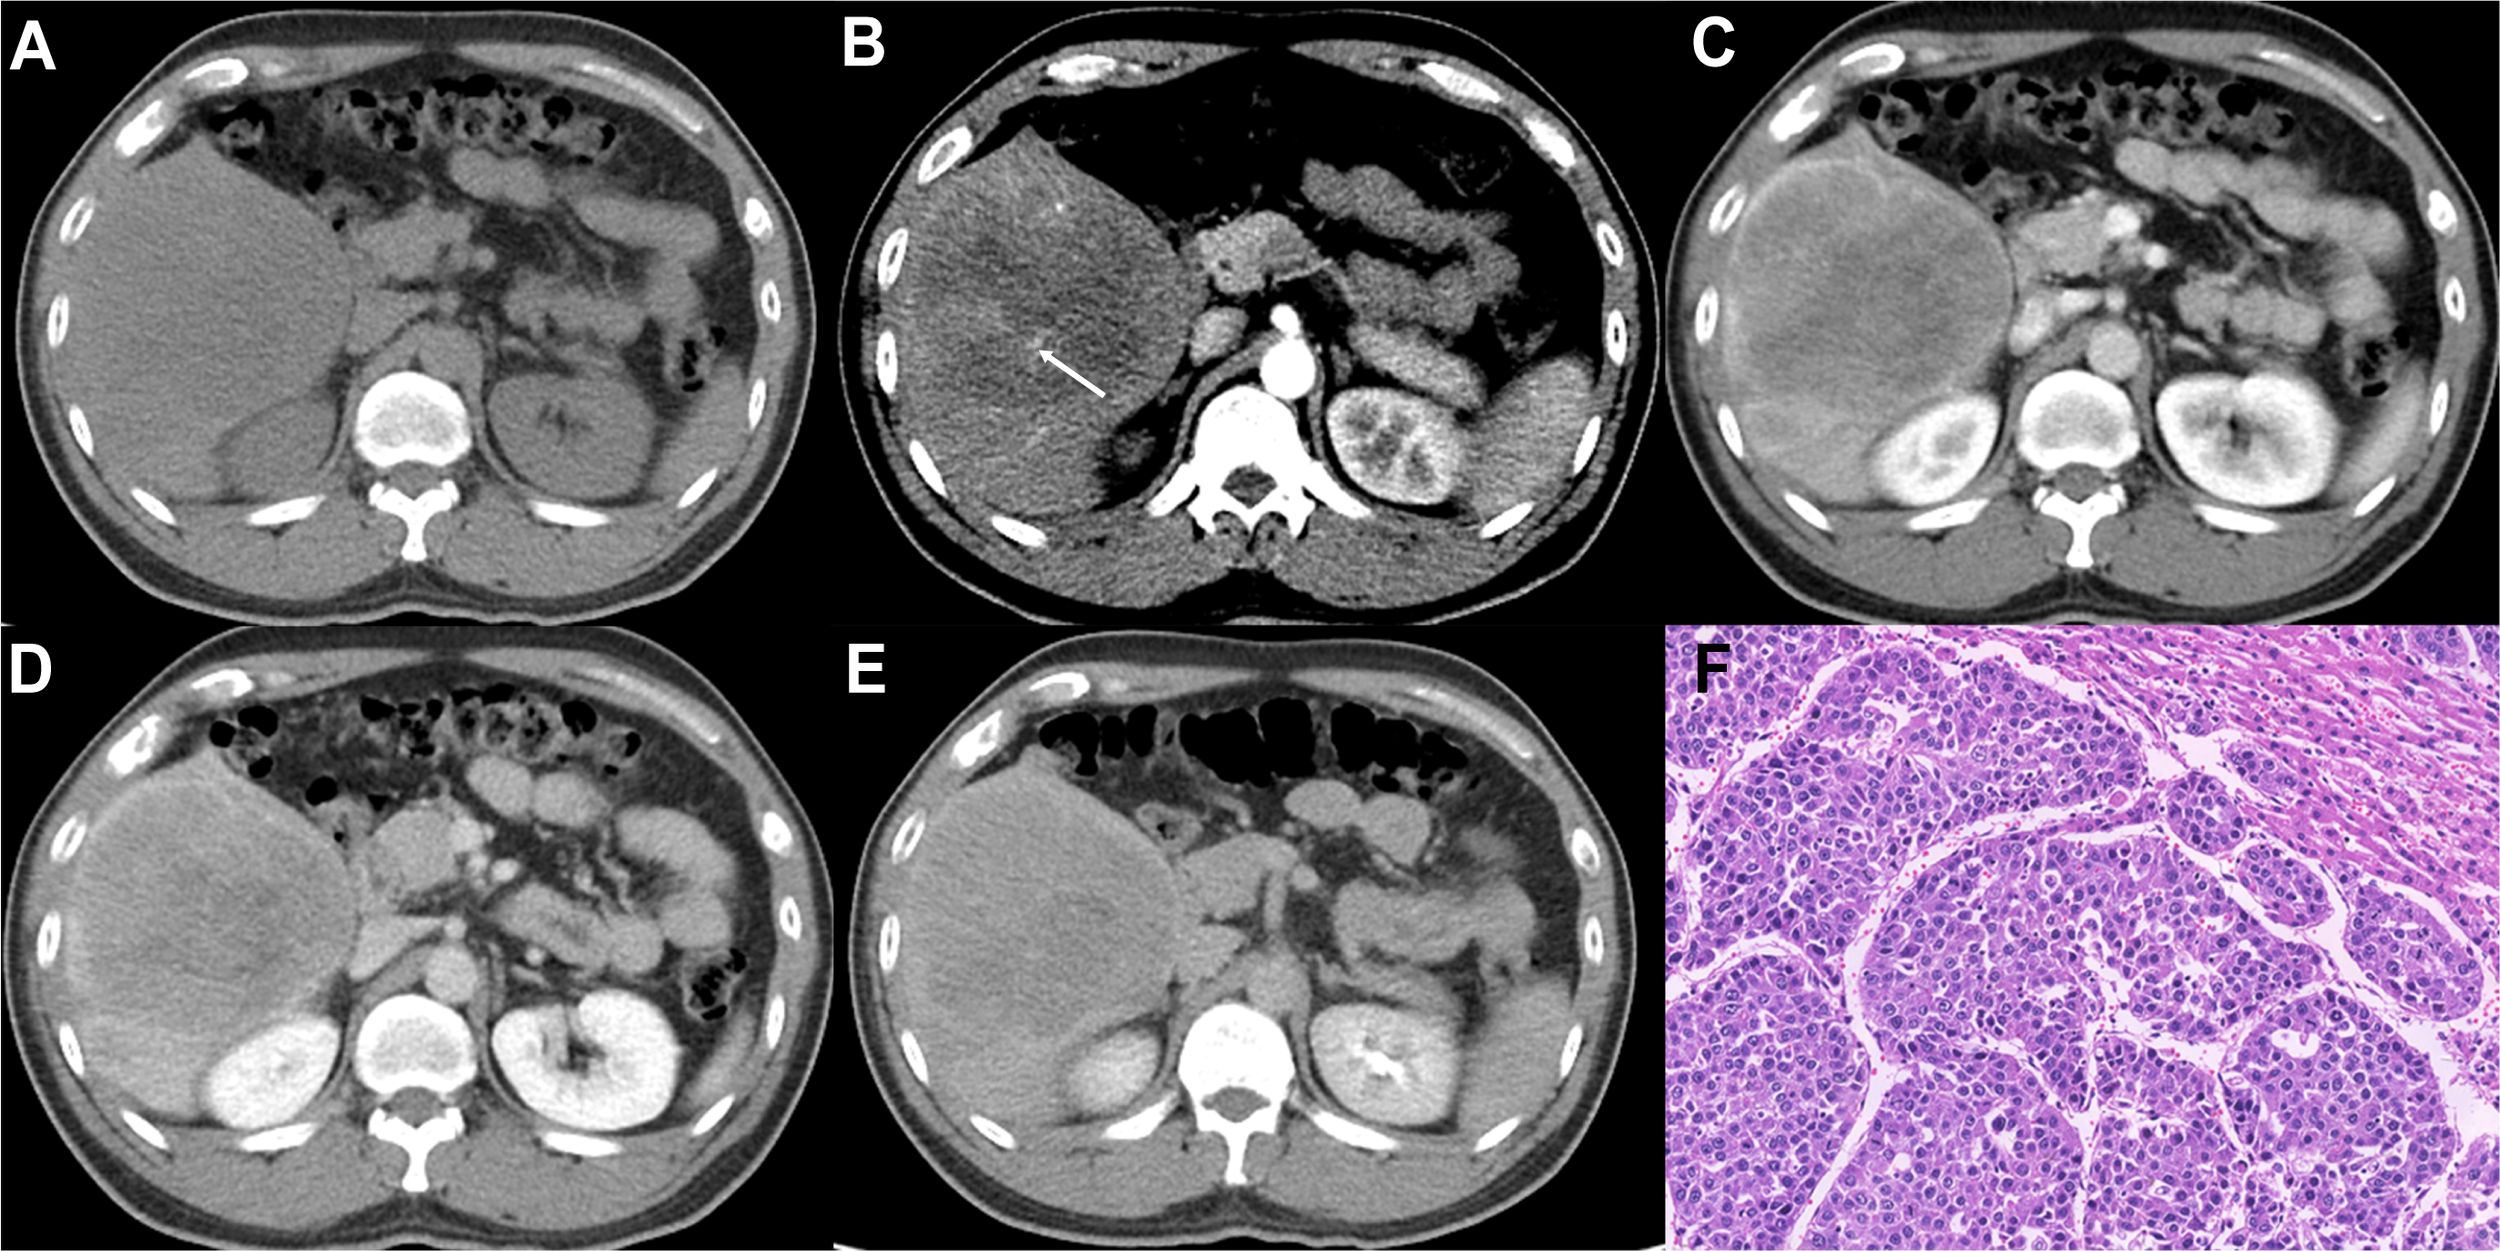

Figure 2

Imaging features and pathological information of a 37-year-old male MTM-HCC patient with an AFP level of 245,658 ng/mL and hemoglobin of 176 g/L. Multiphase axial contrast-enhanced CT (CECT) displays low attenuation in the unenhanced phase (A), the intratumor artery (white arrow) in the early arterial phase (B), rim hyperenhancement (APHE) and intratumor hypoenhancement in the late arterial phase (C), portal venous phase (D), and delay phase (E). Histopathology revealed the predominant thick trabecular structure diagnosed as MTM-HCC (F, original magnification, × 100; hematoxylin-eosin staining).